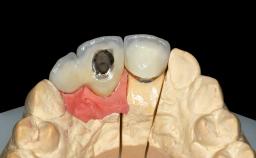

Abutment Type | CAD/CAM |

Prosthesis Type | FDP |